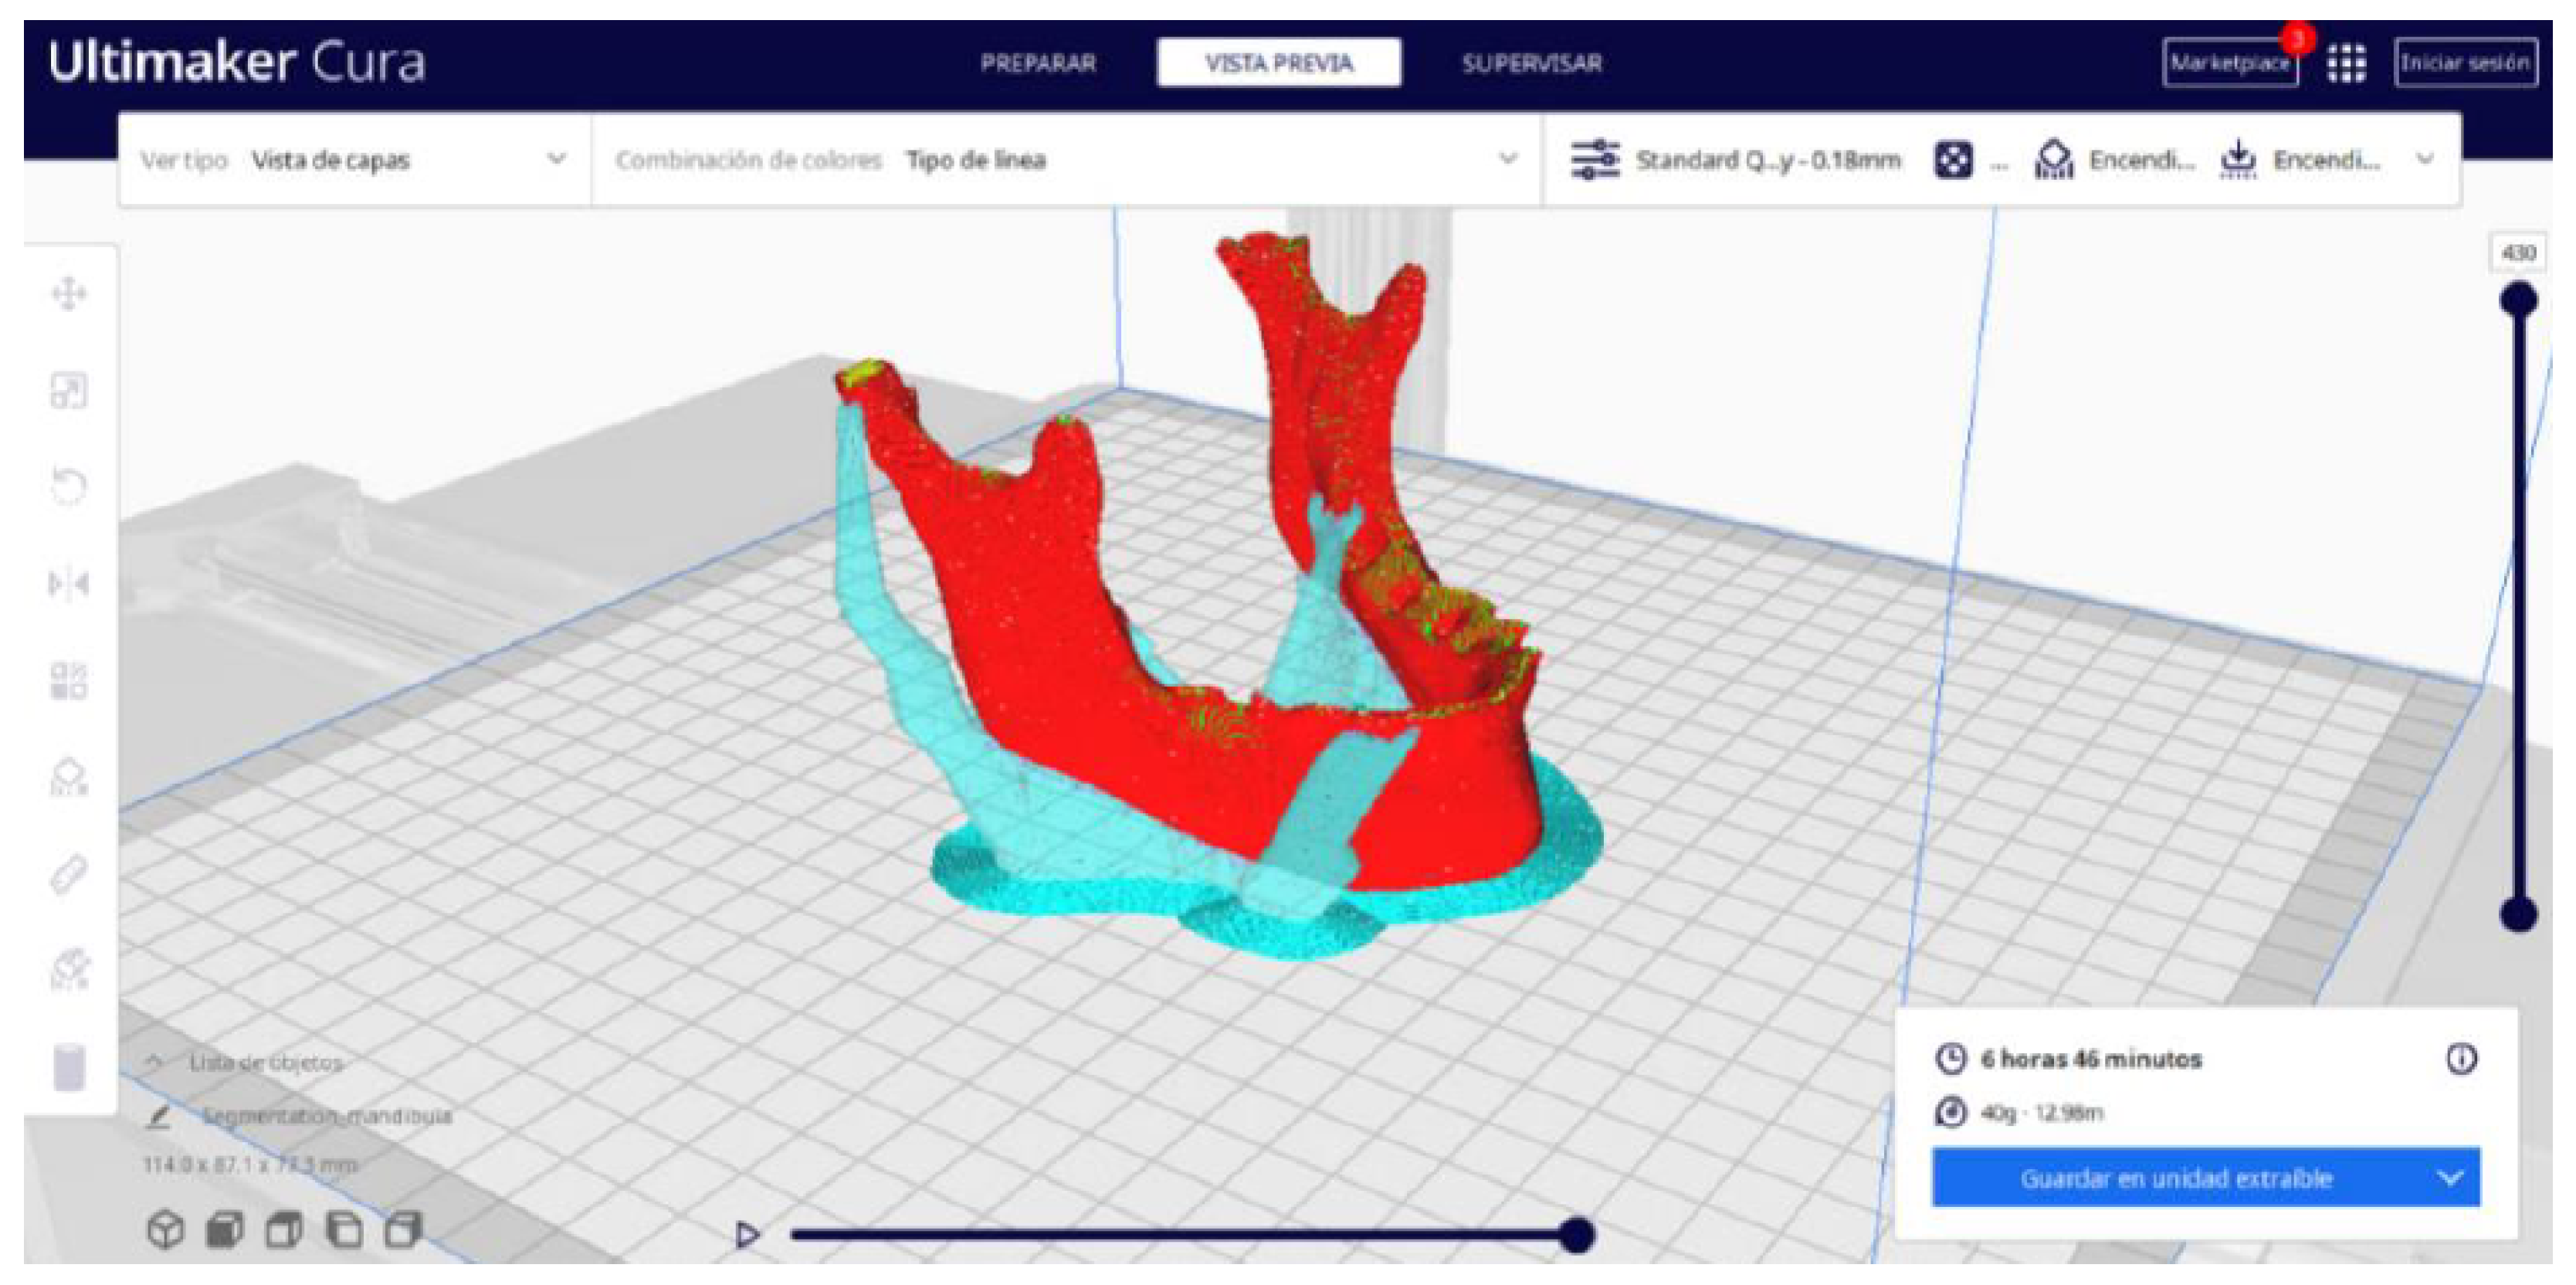

2.2. STL-to-GCODE File Conversion

- Choose the appropriate support structure type and pattern to ensure the successful printing of complex geometries, adjusting the adhesion to the build plate as necessary.

- In order to continue the STL file to GCODE conversion process, select the “Segmentation” option in Ultimaker Cura.

- The segmentation tool provides valuable information such as the estimated model weight and estimated printing time, among other crucial data.

- Once the segmentation is complete, go to the “Preview” option. Here, a sidebar will appear on the right side of the screen, giving you the ability to preview the materialisation process layer by layer, from the base to the top of the model.

3.2. Human Lower Jaw

3.2.2. STL-to-GCODE Files